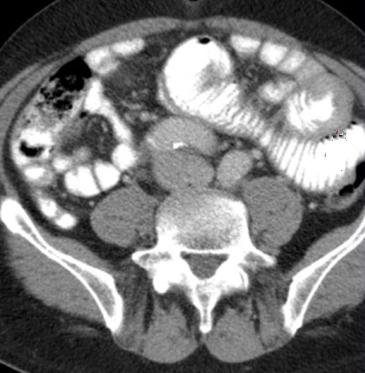

La CT scanner de l'abdomen du

tube digestif et des voies biliaire :

La Tomodensitometrie computerisation

( CT scanner ) simple se base sur la

balayage d'une faisceau de rayon x sur le patient en plusieures de angles inclinees sur une

meme plan de coupe . Les signales a receuillir par detecteur de rayon

X a

cote opposee du faisceau , seraient traites en informatique

numerique a aide d'outils mathematiques ( algorithmes) ce

qui permettre de recontruire en image un coupe anatomique .

Cette methode est plus couteuse que echographie mais est

l'examen de deuxieme intention pour exploration de la

pathologie du foie , des voies biliaires et de pancreas

. Sa resolution et image de receuillir etre bien et sa champ

de visuelle est plus large que echographie .Ce qui ainsi

peut utilise de recherche de adenopathie et de extention

locale ou metastasique de cancer de voie biliaire .

...Recontruction multiplanaire

et resolution spaciale en trois plans pour explorer et les

coupes doient fine de moins 3mm a low dose . L'etude du grele par CT scanner necessite un opacification

des anses intestinales par produit de contrast a ingestion

simple par la bouche : enterographie avec tomodensitometrie

ou intillation par sondage : enteroclyse avec scanner .

Diagnostic des pathologies du grele se met sur etude de

epaisseur de la paroi du grele ou de defaut de remplissage de

la lumiere intestinale .

| |

|

Coupe axiale de estoma (

normale ) |

Coupe axiale de estoma ( ulcere ) |

images enteroclyse +scanner |

L'indication de CT scanner digestive

sont vastes : ils sont necessaire pour un grand nombre de

pathologies digestive , les lesions inflamatoires , tumorales ,

traumatiques , vasculaires ou mecaniques. Et encore a aide du CT

scanner tous les organes pleines abdominaux , les vaisseaux

, les aires ganglionaires et la graisse intra abdominale

sont en meme de explore . La tomodensitometrie helicoidale : combinant

la rotation continue des detecteurs du tube de rayon X avec

un deplacement longitudinal du patient , ce qui permet

acquisition en quelques seconds d'un volume de lesion .